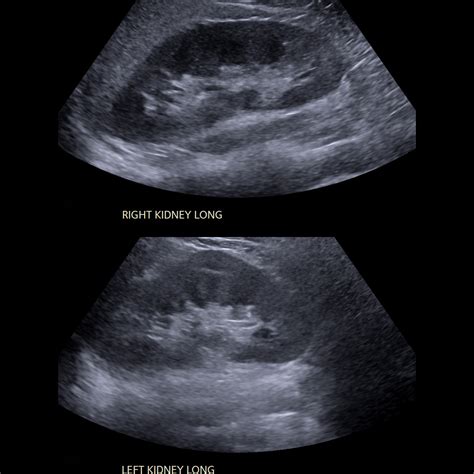

Normal Ultrasound Of Kidneys

A kidney ultrasound, or sonography, uses high-frequency sound waves to create images of the kidneys, ureters, and bladder. It is frequently the first line of investigation for clinicians because it is safe, widely available, and highly effective at identifying structural abnormalities. When a radiologist reviews the images, they are looking for specific markers that indicate health versus disease.

When you receive a report stating you have a Normal Ultrasound Of Kidneys, it means that the radiologist has evaluated several specific parameters and found them to be within expected clinical ranges. The kidneys are evaluated for their size, shape, position, and internal architecture. If these elements match the standard anatomical profile for a healthy adult, the organ is considered functioning structurally as intended.

Primary areas examined during the scan include:

• Cortical Echogenicity: The brightness of the outer layer of the kidney.

• Corticomedullary Differentiation: The clear visual distinction between the outer cortex and the inner medulla.

• Size and Dimensions: Ensuring the kidneys are not too small (atrophied) or abnormally enlarged.

• Presence of Hydronephrosis: Checking for swelling caused by a backup of urine.

• Masses or Cysts: Looking for abnormal growths, tumors, or fluid-filled sacs.

What Constitutes Normal Findings?

The term Normal Ultrasound Of Kidneys is standardized by medical imaging professionals. During the procedure, the sonographer maneuvers a transducer over your abdomen and back, capturing images from multiple angles. The following table summarizes what clinicians identify as normal characteristics compared to potential abnormal findings.

Parameter Expected Normal Finding Potential Abnormal Finding

Kidney Size Typically 9–12 cm in length Small/shrunken (chronic disease) or enlarged

Echogenicity Less than or equal to the liver/spleen Increased (suggests parenchymal disease)

Calyceal System No dilation or collection of fluid Hydronephrosis (dilation/obstruction)

Renal Outline Smooth, regular borders Irregular, lobulated, or scarred

Fluid Presence None, unless simple benign cysts Complex masses or stones (calculi)